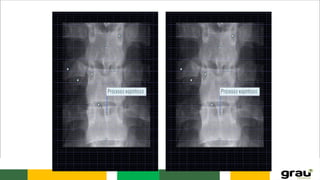

C. LOMBAR

5 vértebras (L1 a L5)

Corpo robusto

Processo espinhoso laminar

L2

L3-L4

C. LOMBAR 5 vértebras(L1 a L5) Corpo robusto Processo espinhoso laminar L2 L3-L4